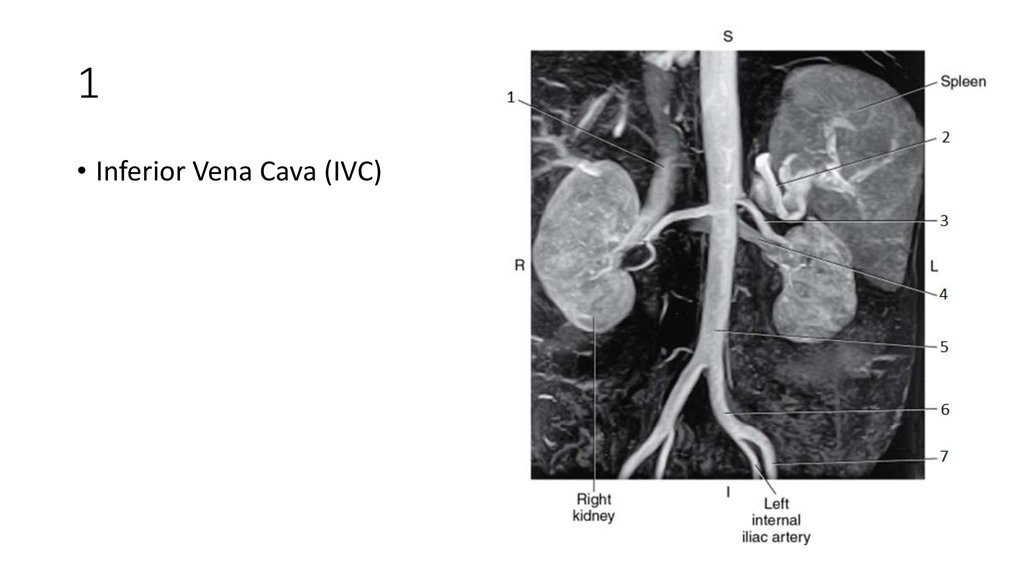

62. 1

• Inferior Vena Cava (IVC)

64. 2

• Splenic Artery

66. 3

• Left Renal Artery

68. 4

• Left Renal Vein

69. 4

71. 5

• Aorta

72. 6

• Left Common Iliac Artery

74. 7

• Left External Iliac Artery